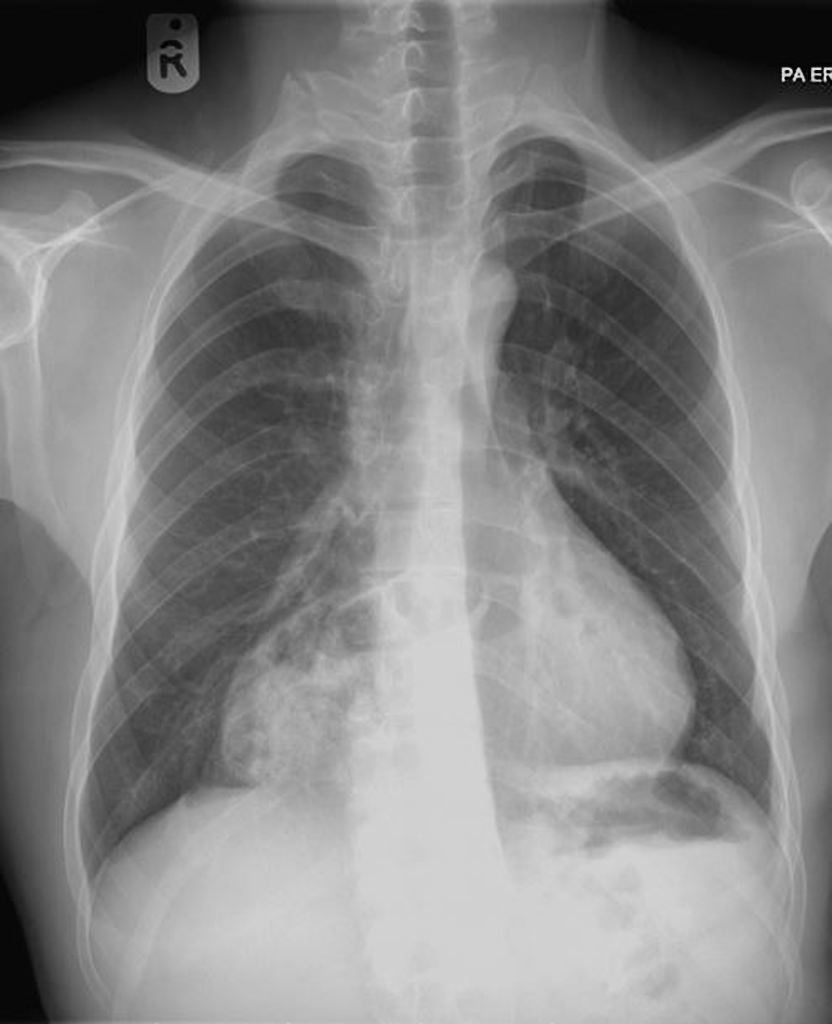

75 ANOS DE IDADE, REFERE DOR TORÁCICA

duplo contorno da borda cardíaca esquerda devido a dilatação da aorta ascendente

ANEURISMA DE AORTA ASCENDENTE